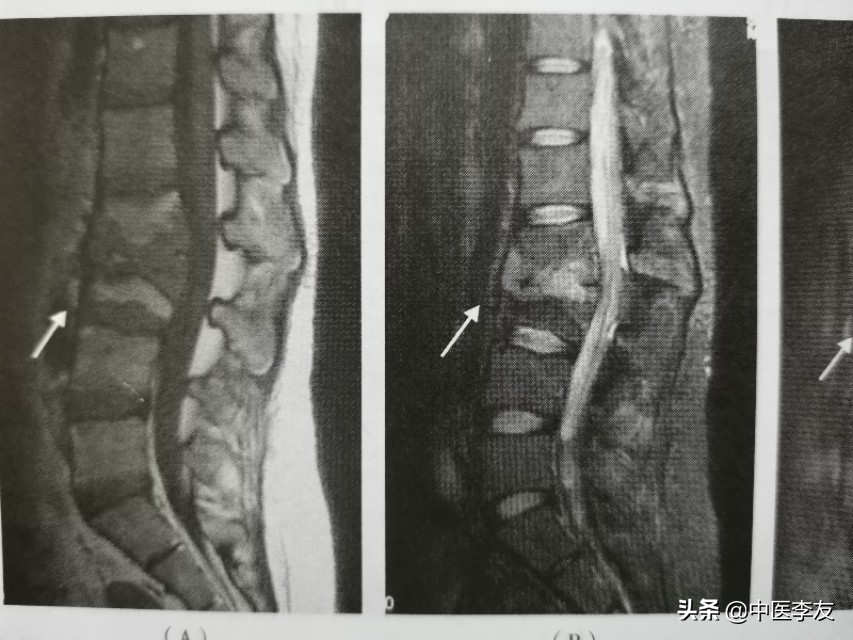

3.MRI,表现是显示脊椎结核病灶和范围最敏感的方法,可发现椎体内早期炎性水肿。病灶T1WI表现为低信号,T2WI多表现为混杂高信号;GD-DTPA增强不均匀强化。脓肿和肉芽肿在T1WI上呈低信号,T2WI多为混杂高信号,部分均匀高信号,增强检查肉芽肿不均匀,均匀强化,脓肿壁薄且均匀的环状强化。

腰椎结核

在脊柱结核发病的时候,一般有两种类型:①中央型,病灶起于椎体松质骨,死骨吸收后形成空洞。②边缘性,病变破坏椎体边缘和椎间盘组织,椎体呈楔形破坏,椎间隙变狭窄,形成脓肿,继而形成椎旁脓肿,并向组织间隙流向远处。